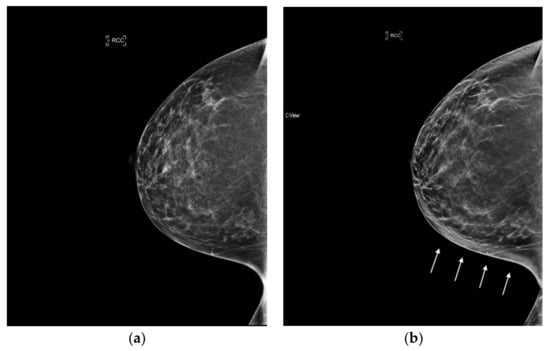

6.4. Masses and Asymmetries

With 2D FFDM, overlapping tissue may obscure the margins of masses and create asymmetrical areas of tissue. One of the benefits of tomosynthesis is the improvement in margin analysis of masses as this tissue is cleared away. This information is passed onto the synthesized image as it is created from the DBT data set, which can lead to clearer conspicuity of masses and their margins (Figure 4). Potentially false positive asymmetries can also be resolved on tomosynthesis. Since s2D is always read in conjunction with DBT, these benefits remain when synthesized mammography is used. (Figure 5).

Figure 5.

Indeterminate asymmetry seen on 2D FFDM is less prominent on synthesized mammography and resolved on DBT slices; no recall was necessary. (a) 2D FFDM (b) s2D.

When stratified by mammographic finding, recall rates were shown to be lower with s2D+DBT for calcified lesions and asymmetries, with no significant change in recalls of architectural distortion or masses. This result could be because AD and masses are best resolved on DBT images, which were utilized in both the synthesized and FFDM groups [28].